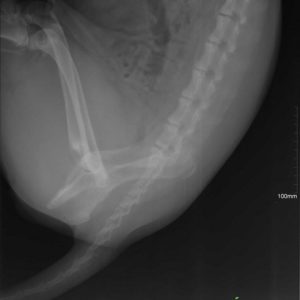

Ismét hálával van teli a szívünk- köszönjük Alexander Englertnek, hogy Zora műtétjét finanszírozta!

Zora túl van a műtéten és 5 nap után újra velünk van a menhelyen! A kedve jó, nincsenek fájdalmai és reméljük a 2 hónap pihenő után végre felszabadultan játszhat majd a többiekkel!